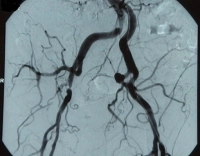

Ejemplo de película: TASC B, estenosis de alto grado de la A. iliaca externa y estenosis del 50 % de la A. iliaca communis derecha, clínicamente AVK estadio IIb según Fontaine → Indicación para la reconstrucción endovascular